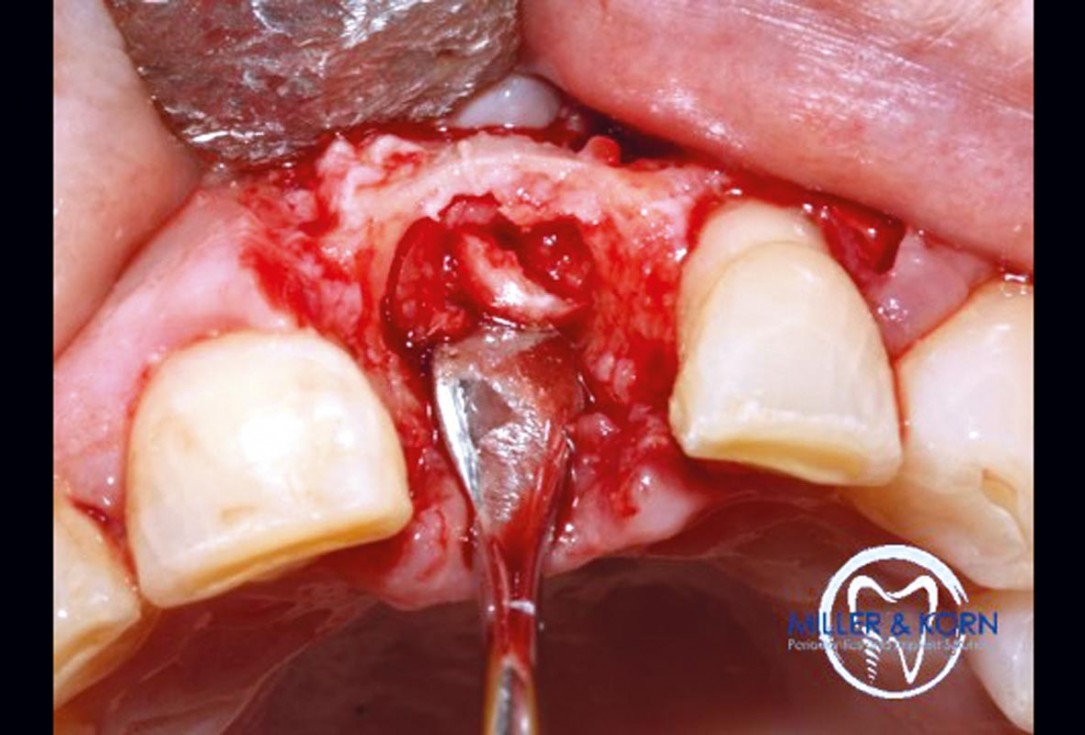

14/39 - Retrieval of autologous bone chipsImmediate implant placement and correction of horizontal and vertical bone loss using an allograft bone ring, cerabone® and Jason® membrane - Drs. Miller and Korn